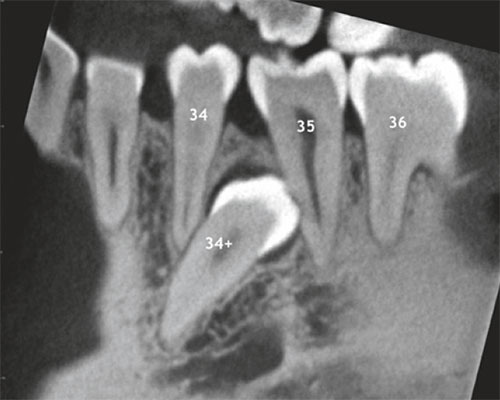

Überzähliger, retinierter Prämolar (34+) mit Resorption der mesialen Wurzel 35 (sagittales und axiales DVT-Schnittbild).